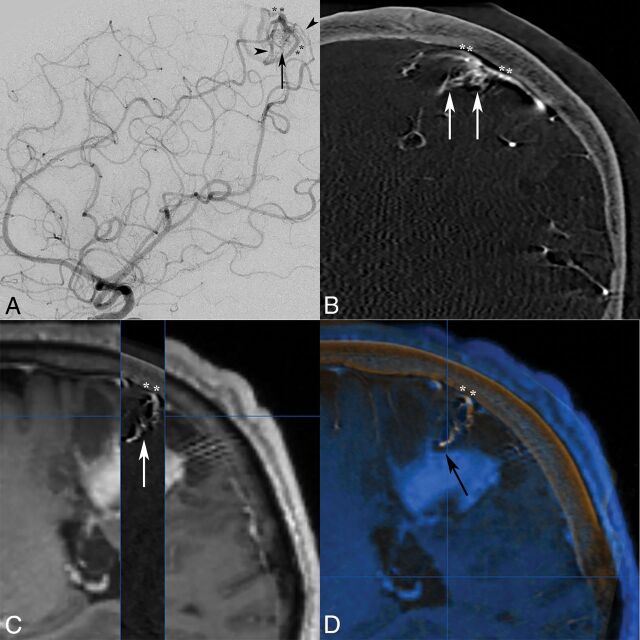

A 50-year-old man presented to an outside institution with confusion followed by right hemiparesis. Initial CT/MR imaging discovered a left parietal cortical hemorrhage, which was conservatively managed. Delayed 2-month MR imaging findings were negative, but subsequent DSA reported a left parietal pial AVF, and embolization was planned. At our institution, a repeat DSA with the 3DRA/IA-CBCTA technique revealed a superficial left parietal mAVM with a nidus measuring <1 cm (Fig 3A, B). Left frontoparietal paramedian craniotomy and microsurgical resection were performed with IA-CBCTA imaging integrated into the neuronavigation system (Fig 3C, D).

Fig 3.

Lateral DSA (A) and coronal IA-CBCTA reconstruction (B) images both demonstrate a small <1-cm micronidus (arrows), supplied by tortuous parietal branches of the pericallosal anterior cerebral artery and inferior division of the MCA (arrowheads), with early venous drainage into bifurcating cortical veins (double asterisks). Although both observers did not report the improved diagnostic value of IA-CBCTA in this case, both neurosurgeons reported increased confidence in treatment planning, and IA-CBCTA was incorporated into the neuronavigation system for microsurgical resection. 3D IA-CBCTA and MR imaging datasets were merged with sagittal overlay (C) delineating the micronidus (arrow) and draining cortical vein (double asterisks) complex in relation to the adjacent hemorrhage. Both datasets were imported into the intraoperative neuronavigation system (D, BrainLAB), allowing anatomic localization of the micronidus within a specific sulcus guiding the surgical approach as well as the presumed deep nidal rupture site abutting the hematoma (black arrow).